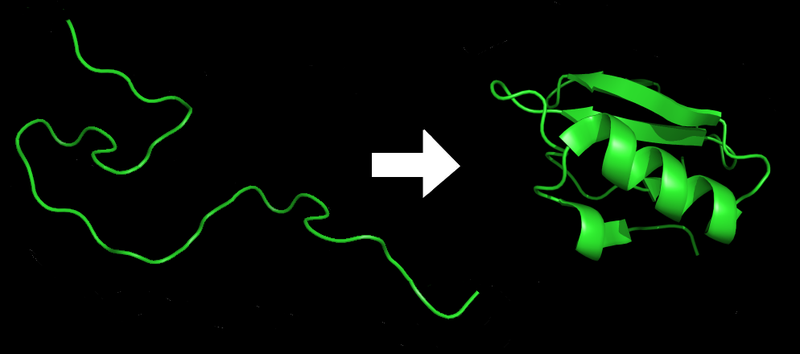

Although DNA is at the kernel, it’s not the entire story behind disease. DNA directs proteins (utilizing RNA as an intermediary to transcribe and translate instructions), and proteins perform as directed. But, in the process, “they can become tangled…leading to disorders such as diabetes, Parkinson’s and Alzheimer’s disease”. [12] For this reason, predicting the shape of a protein is vitally important to understanding its function — a task historically of extreme difficulty.

In 2011, researchers crowdsourced the matter, turning to gamers to help find solutions to protein folding problems. Within three weeks, the combined efforts of gamers and researchers resulted in “crucial insights to solve the structure of a protein-sniping enzyme critical for reproduction of the AIDS virus” — a feat that had stumped scientists for a decade. [13] According to Scientific American at the time, “humans retain an edge over computers when complex problems require intuition and leaps of insight rather than brute calculation”.

Protein Folding from Wikimedia Commons

Apparently, that edge didn’t last the remainder of the decade. Google’s AlphaFold, a deep learning algorithm trained on the aforementioned Foldit game, beat out 98 competitors in a protein-folding challenge by an enormous margin. “Predicting the most accurate structure for 25 out of 43 proteins, compared with three out of 43 for the second placed team”. [14] Perhaps more importantly, the program went from taking weeks to supply a prediction to doing so in a matter of hours. With more data and more practice, AI has proven it will gain accuracy and efficiency.

Insight into protein folding allows researchers to peer not only into the function of hereditable diseases, but also how to develop drugs to treat them. As reported by the New York Times, “If scientists can predict a protein’s shape, they can better determine how other molecules will ‘bind’ to it”. Made more widely available, tools like AlphaFold can drastically decrease the amount of time and money required to develop treatments for previously incurable diseases.

While AlphaFold’s dramatic win signals AI’s increasing importance in biochemical research, not all are convinced that machines and those developing them will be able to provide all of the answers. As Dr. David Baker, director of the Institute for Protein Design at the University of Washington, expresses to the New York Times: “creating proteins is more important to drug discovery than the ‘folding’ methods being explored,” a task he believes AlphaFold is not well-suited to complete.